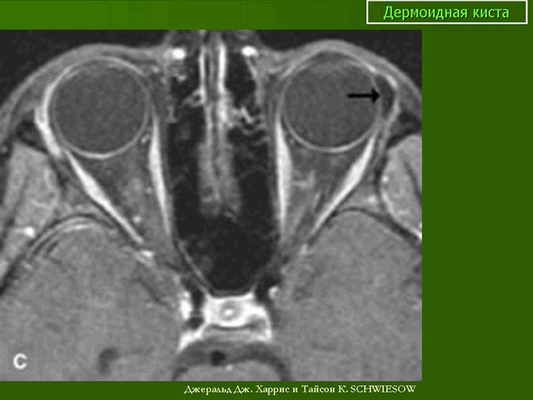

Наиболее детальную информацию о размерах, соотношении с прилежащими структурами, содержимом кистозного образования помогает оценить компьютерная или магнитно-резонансная томография (рис.2). В зависимости от содержимого кистозные образования орбит (плотности и содержания жирового компонента) на КТ и МРТ выглядят по-разному, не накапливают контрастный препарат, имеют четкие контуры и капсулу, в 15% случаев имеют кальцинаты (хорошо видны на КТ). МРТ и КТ необходимо для предоперационного планирования, чтобы полноценно оценить весь объём образования (иногда определяется и глубокий компонент, которым может быть источником рецидива).

МРТ орбит. Дополнительное тканевое образование с жировым компонентом (указано стрелочкой), гиперинтенсивное на Т1-ВИ (первое изображение), гипоинтенсивное на Т2-ВИ с жироподавлением (второе изображение), не накапливающее контрастный препарат Т1-ВИ с жироподавлением и контрастным усилением (последнее в ряду изображение).